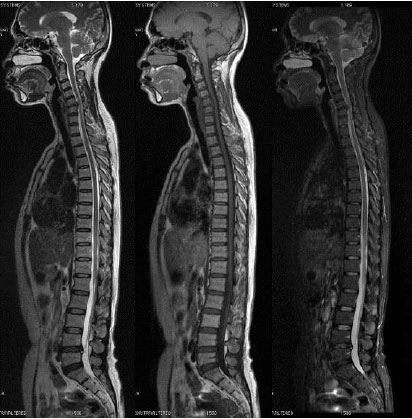

全脊柱磁共振成像

全脊柱磁共振成像(full spine magnetic resonance imaging)是指对全脊柱的部位进行核磁共振检查。

全脊柱分为4个部分,全脊柱包括颈椎,胸椎、腰椎以及骶尾椎,全脊柱的核磁共振,就是对这些部位全部进行核磁共振检查,核磁共振对神经系统病变和脊柱关节等部位的病变诊断,具有非常重要的价值。全脊柱核磁共振检查能够完整的显示椎管里脊髓,脊椎以及周围韧带等的病变。对脊柱各结构能够清晰、直观、完整的展现出来。对一些脊柱相关疾病,例如颈腰综合症累及范围、脊髓空洞症累及范围、前后韧带骨化范围以及椎管内囊肿或者肿瘤侵犯范围均能较好的显示,这是某一单项部位检查代替不了的。